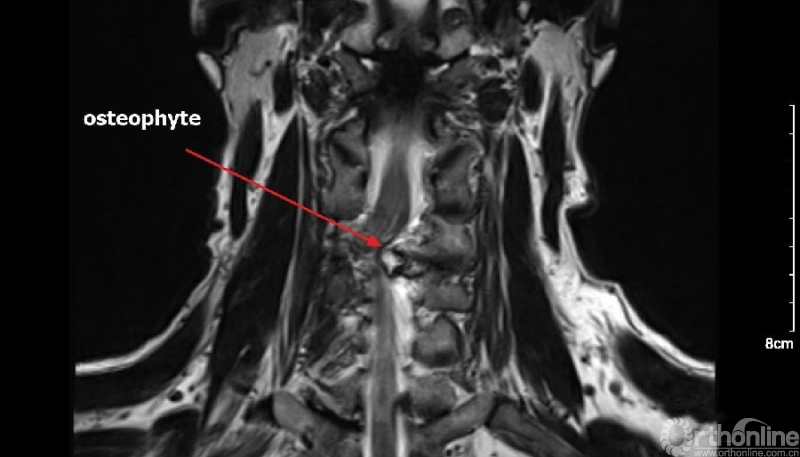

入院查体患者四肢肌张力高,双侧hoffman阳性。CT及MRI检查提示C4/5左侧关节突内缘有一巨大骨块(15mm*16mm),相应节段椎管严重狭窄。椎管内骨块的前端还有一游离骨块。

影像学资料